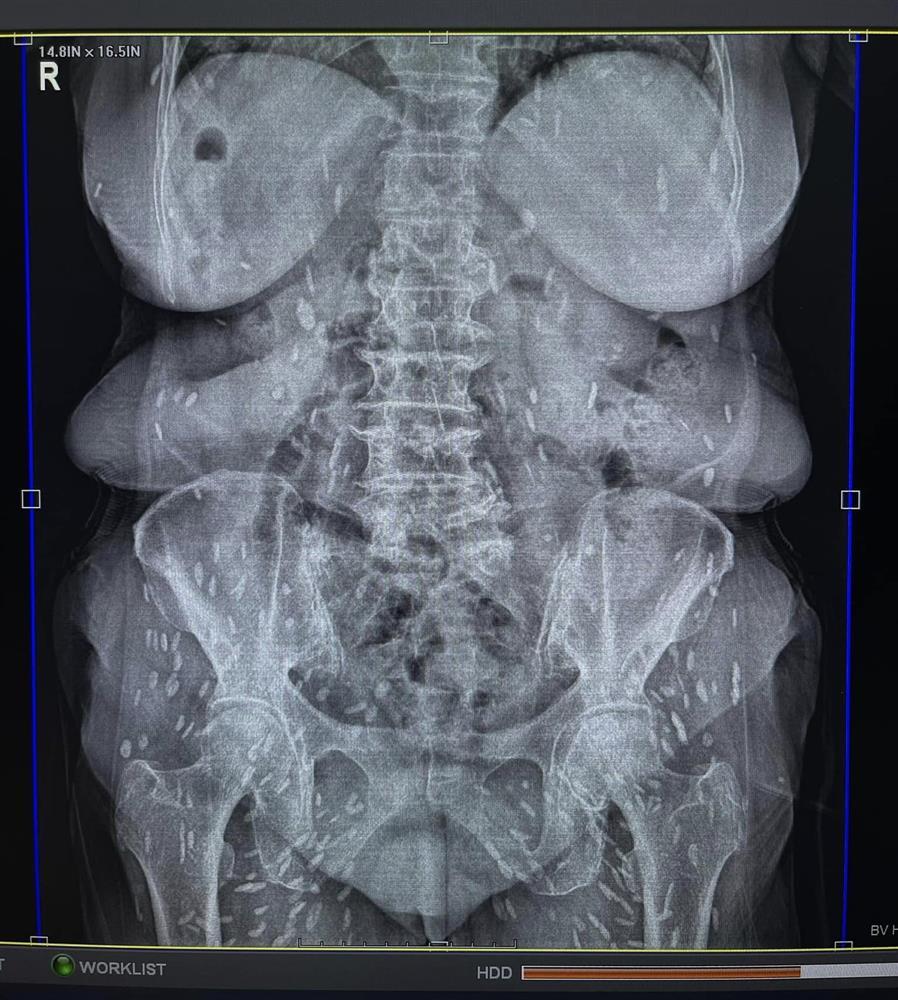

Khi đến khám, cụ được bác sĩ chỉ định thực hiện chụp X-quang. Kết quả phát hiện thấy hình ảnh nhiều kén sán hình dạng kích cỡ như hạt gạo nằm rải rác trong các mô, cơ trên phim trường vùng ngực.

Sau khi kiểm tra tổng quát thêm vùng bụng, hai chi dưới thì phát hiện thấy rất nhiều kén sán mật độ dày toàn bộ cơ thể.

Sau khi khai thác tiền sử dịch tễ cùng hình ảnh trên phim X-quang, bác sĩ chẩn đoán sơ bộ cụ bà N.T.H bị nhiễm kén sán dây lợn. Những nang kén này có thể đã tồn tại trong cơ thể người bệnh từ 5 - 7 năm.